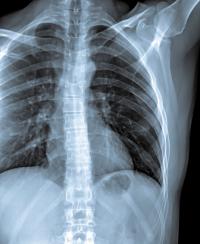

IPF causes scar tissue to build up in the lungs, impairing the ability to breath. Eventually the entire lung fills with scar tissue, and the loss of lung function is relentless.